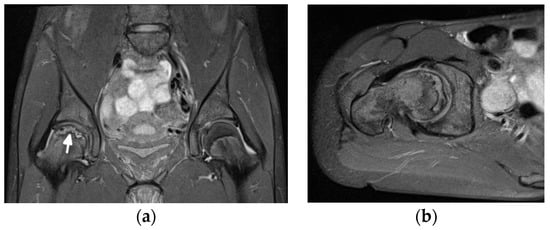

Diagnosis of ON and fractures is based on MRI in early stages (Figure 12) and radiography in advanced stages, like in adults.

Figure 12.

Magnetic resonance (MR) imaging of the femoral head osteonecrosis (ON) in a 14-year-old female with juvenile systemic lupus erythematosus. (a) Coronal and (b) axial proton density-weighted with fat saturation (right) MR images of the pelvis and right hip show a geographic serpiginous lesion in the right femoral head, with a bone marrow edema irregular contour and demarcation line consistent with ON (arrow).